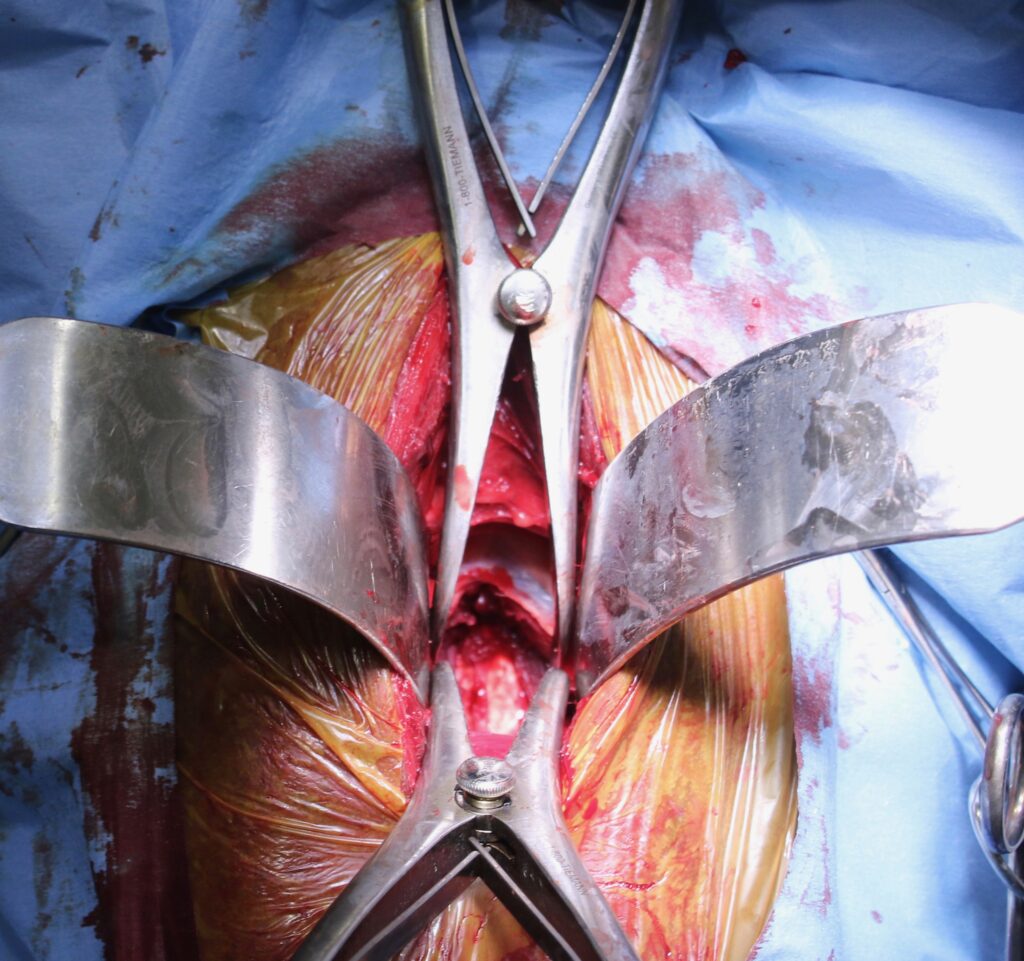

Obrázek 2c: Postižená kost a meziobratlová ploténka byly chirurgicky odstraněny a oba obratle byly spojeny pomocí ploténky a šroubů

Známý dostihový kůň jménem Seattle Slew začal trpět závažnou ataxií. Dr. Grant ho operoval s použitím vylepšené protézy a kůň poté prožil ještě velmi úspěšnou dostihovou kariéru. Kůň je při artrodéze operován v celkové anestezii a je položený na zádech (obr. 10–13).

Obrázek 10: Foto z průběhu operace, 15centimetrový řez

Obrázek 11: Odtažení svalů krku pro uvolnění přístupu k obratlům

Relativně malý, asi patnácticentimetrový řez se provádí ve spodní části krku (obr. 10) v úrovni problematického místa. Průdušnice a svaly jsou odtaženy stranou a přístup ke krčním obratlům je uvolněn (obr. 11). Titanová protéza je umístěna pod rentgenologickou kontrolou tak, aby dokonale stabilizovala oba obratle (obr. 12). Pokud se vyskytuje více míst, kde dochází ke zvýšení tlaku na míchu, je možné spojit i více obratlů (obr. 9). Tento chirurgický zákrok je v Equitomu zcela běžný a zabere přibližně jeden a půl hodiny (obr. 13).